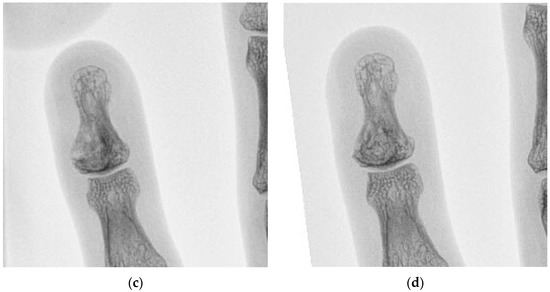

5 | 36 M | 1 | Left little finger P3 | 10 | Enchondroma | 25 |

7 | 71 M | 2 | Right middle finger P3 | 20 | Epidermoid cyst | 27 |